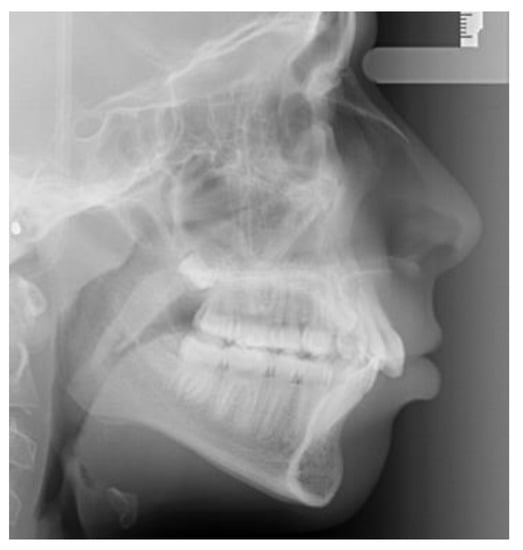

Lateral cephalometric radiographs were used to measure skeletal relationship angle (ANB) and evaluate PP (Figure 1), sella bridging (Figure 2) and atlas posterior arch deficiency (Figure 3).

The evaluation of the sagittal length of the radiographic image of the atlas posterior arch was also made, so as to define its level of formation: fully formed or deficient.

Figure 3. Deficient posterior atlas arch.